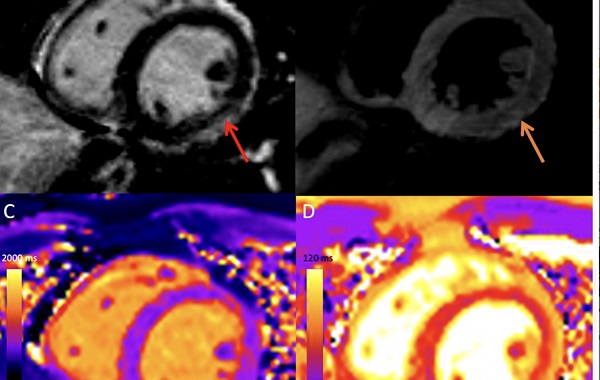

- MRI cung cấp hình ảnh tim tốt hơn các phương pháp khác trong một số điều kiện nhất định, đặc biệt là các bất thường liên quan đến cơ tim.

- MRI có giá trị chẩn đoán cao trong các tình trạng giải phẫu tim bất thường (dị tật tim bẩm sinh), bất thường chức năng tim (suy van), khối u và bệnh liên quan đến động mạch vành.